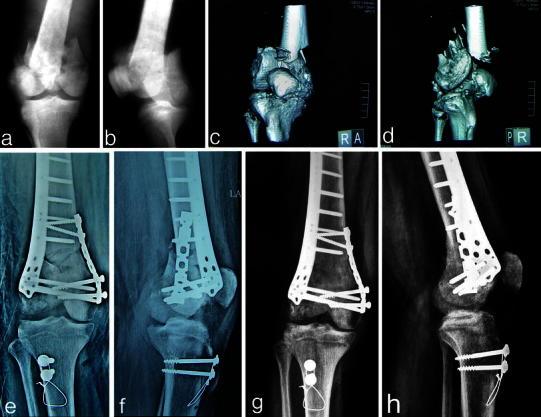

Highly unstable complex C3-type distal femur fracture: can double plating via a modified Olerud extensile approach be a standby solution?

Multiplanar complex C3-type unstable distal femoral fractures present many challenges in terms of approach and fixation. This prospective study investigates a possible solution to these problems through double plating with autogenous bone grafting via a modified Olerud extensile approach.

Twelve patients with closed C3-type injuries were included; eight of them were male, and their mean age was 33.5 years (range 22-44 years). Mechanism of injury was road traffic accident (RTA) in nine patients and fall from height in the other three cases. Eight cases were operated during the first week and four cases during the second week after injury. Mean follow-up was 13.7 months (range 11-18 months).

Mean radiological healing time was 18.3 weeks (range 12-28 weeks), and all cases had good radiological healing without recorded nonunion or malunion. Clinically, two cases (16.7 %) had excellent results, five cases (41.7 %) had good results, three cases (25 %) had fair results, and two cases (16.7 %) had poor results. No cases developed skin necrosis, deep infection, bone collapse, or implant failure. However, two cases (16.7 %) had limited knee flexion to 90° and required subsequent quadricepsplasty.

Use of this modified highly invasive approach facilitated anatomical reconstruction of C3-type complex distal femoral fractures with lower expected complication rate and acceptable clinical outcome, especially offering good reconstruction of the suprapatellar pouch area. It can be considered as a standby solution for managing these difficult injuries.